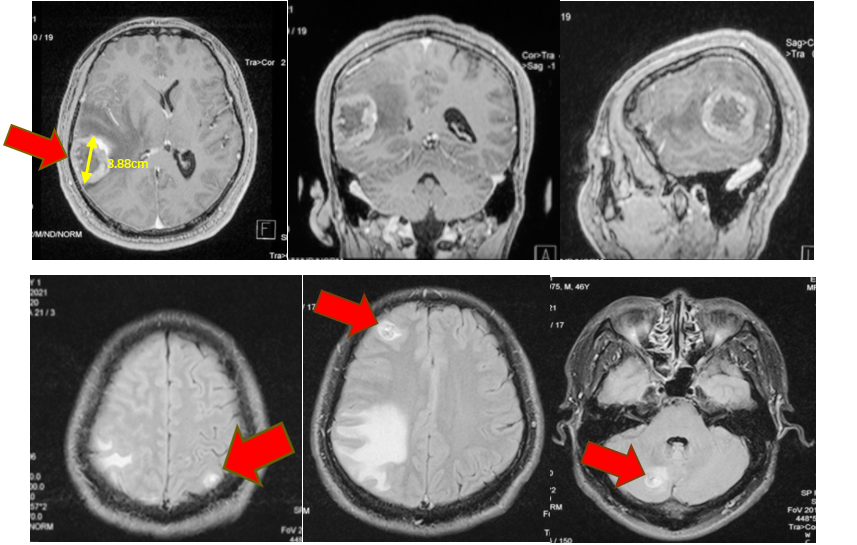

患者为46岁中年男性,主因前额搏动性疼痛1月余,加重1周至当地医院就诊,颅脑CT检查提示右侧颞顶叶占位:转移瘤?,入院完善相关术前检查后发现该患者肺部占位、颅内多发占位,怀疑肺癌脑转移瘤。 结合患者一般情况及影像学检查分析病情。认为颅内右侧颞顶叶肿瘤占位效应明显,导致中线移位,脑室受压,肿瘤进展较快,有进一步增大可能,严重时可能出现脑疝,危及生命。且该占位最大径>3cm,放化疗效果差,同时手术可明确肿瘤性质,因此计划手术切除右颞顶叶占位,其余颅内占位较小,占位效应不明显。肺部占位可在明确组织病理及分子病理后再行治疗。 颅脑磁共振提示颅内多发占位 胸部CT提示右上肺尖段占位 排除绝对手术禁忌后于2021年11月10日行全麻下左侧卧位右侧颞顶叶占位切除术。术后患者病情平稳,未见新发神经功能障碍,查体同术前。术后病理提示:符合低分化腺癌,考虑为肺来源。免疫组化提示:CK7(+)、NapsinA(+)、TTF-1(+)、ALK(ventana)(-)、PD-L1(SP263)(30%)。分子病理提示:EGFR 19缺失突变。 术区CT 出院后患者至我院脑转移瘤多学科联合门诊拟定下一步诊疗方案。脑转移瘤MDT专家团队联合为转移瘤患者会诊,各学科专家详细询问了患者的相关病情及诊疗经过,并仔细阅读了影像学检查及实验室检验结果,从各自专业角度,结合患者整体病情,提出了各自相关专业的处理方案以及为患者制定了全面、精准、规范的诊疗计划: 神经外科冯世宇主任:患者脑转移瘤术后恢复良好,建议下一步综合治疗。 放射科肖华锋主任:阅患者术前MRI和术后CT提示颅内多发转移瘤,右侧颞顶叶转移瘤术后改变。肺部CT提示右上肺肺癌,建议肺部CT增强扫描,颅脑MR增强扫描,定期复查。 胸外科马永富主任:病史已阅,建议完善胸部增强CT。评价右上肺手术机会。 肿瘤内科吴志勇主任:肺癌脑转移考虑EGFR作为主要驱动基因治疗,结合TP53/ target=_blank class=infotextkey>P53突变,建议应用EGFT TKI+安罗替尼治疗,EGFT TKI首选奥希替尼。 综合意见: 患者就诊联合门诊后积极行化学药物治疗(奥希替尼,口服 80mg 1/日;安罗替尼 口服 8mg 1/日),近日再次至我院复查颅脑磁共振提示病情控制良好(如图)。 右颞顶占位 其余多发占位 肺部占位 病例总结 该患者为46岁中年男性,主因头部疼痛发现颅内多发及肺部占位,高度怀疑肺癌脑转移,但肿瘤性质未明确;颅内右侧颞顶叶肿瘤占位效应明显;肿瘤直径>3cm,放化疗治疗效果较差并且存在风险。手术可快速解除颅内高压症状,消除病灶对周围脑组织的压迫,并且明确肿瘤性质,根据组织病理及分子病理能够寻找肿瘤相关突变基因靶点药物。因此采取了手术切除颅内右侧颞顶叶肿瘤,缓解了占位效应,明确了肿瘤组织病理及分子病理,为患者赢得了下一步综合治疗的时间。 该病例的启示 颅内转移瘤是否手术应进行综合评估,其中包括肿瘤的数量、大小、性质、部位、患者一般情况等。 1、 颅内单发肿瘤最大径>3cm,水肿范围大、占位效应明显时应行手术切除,及时进行减压,挽救患者生命;但其病理性质明确,且对放化疗敏感时,可不首选手术治疗。 2、 颅内多发,若肿瘤数目≤3个,且能完全切除者可行手术治疗;若肿瘤>3个,则建议行放疗、化疗等非手术治疗。但是若占位效应明显、出现梗阻性脑积水、肿瘤卒中甚至脑疝等情况时应行手术切除较大占位病变以达到减压目的,患者赢得下一步治疗的时间以后,再根据组织病理和分子病理,进行化疗或靶向治疗或者放疗等综合治疗。 3、 若肿瘤性质不明确者,应行手术切除或穿刺活检明确组织病理及分子病理,根据其结果可寻找有效的化疗药物或靶向药物等综合治疗的方案。 4、 肿瘤部位较深或位于功能区(如脑干、基底节区、丘脑),评估手术风险高可能带来不可逆的功能障碍,一般不首选手术,可先选择放疗或化疗。 解放军总医院第一医学中心脑转移瘤联合会诊团队由神经外科、肿瘤科、放疗科、放射科、胸外科、乳腺外科等科室专家组成的专家团队,各相关学科专家结合患者的具体情况,制定出最合适患者的个性化的精准治疗方案,提高患者的治疗效果、生活质量以及生存时间。简要病史

术前影像